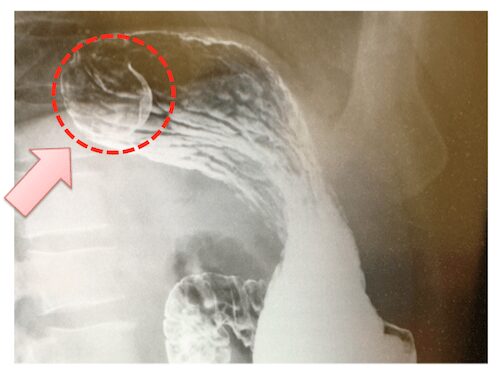

胃X線検査(レントゲン検査)

食道、胃、十二指腸に病気がないか調べる検査です。健診で行われることが多く、造影剤と発泡剤とバリウムを飲み、胃や十二指腸を膨らませた状態でX線検査を行います。これにより、病気の位置や大きさ、臓器の形に異常がないかなどを、大まかに調べることができます。しかし、胃X線検査自体が白黒の影絵であるため、形態的に粘膜下腫瘍を疑うことは比較的容易に出来ますが、粘膜下腫瘍の分類を区別することは困難であり、質的診断能力は高くありません。